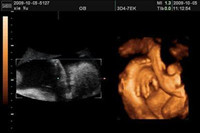

彩超與B超的區(qū)別在哪里呢?彩超與唐氏篩查的區(qū)別又在哪里呢?然而,這些還不是很打緊的問題,最重要的是四維彩超是需要提前預(yù)約才能做的,準(zhǔn)媽媽們知道四維彩超哪里做最好嗎?什么時(shí)...

目前最先進(jìn)的彩色超聲檢測儀器,是大家公認(rèn)的四維彩超,說起四維彩超的優(yōu)點(diǎn)那可多著了,通常懷孕的準(zhǔn)媽媽們在孕期一定要做一次四維彩超,它可以監(jiān)測胎兒在母體的活動(dòng)實(shí)況,...

孕期的各項(xiàng)檢查,準(zhǔn)媽媽們都必須按時(shí)完成,這即是對孕婦自身,也是對胎兒寶寶負(fù)責(zé)。提起四維彩超相信大多數(shù)的媽咪們都很清楚,四維彩超比普通的B超在技術(shù)和等級(jí)上都有一定飛越...